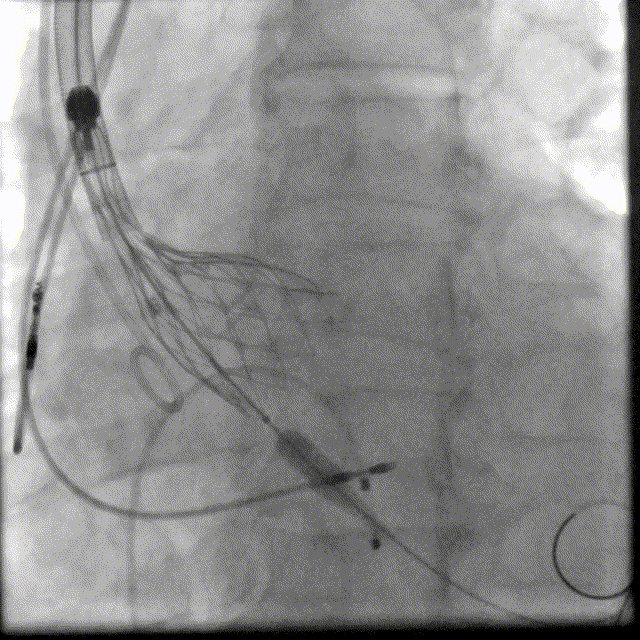

3. 在J型导丝指引下,使用6F pigtail造影导管进入左心室,测得主动脉瓣跨瓣压差15mmHg, 升主动脉血压180/40mmHg, 左心室压力165/5mmHg, 交换为特硬导丝Lunderquist至左心室,结合术前冠脉CT和心脏超声测量的瓣环直径大小,选择VitaFlow Liberty™30可回收瓣膜系统送至主动脉瓣环处,在Pigtail导管定位,主动脉根部造影协助指导下,精准定位,以180次/分快速起搏,逐步释放瓣膜,支架释放后退出导管输送系统,猪尾导管行主动脉根部造影示:人工瓣膜深度4mm, 冠状动脉开口未受影响,食道超声提示无主动脉瓣反流。

VitaFlow Liberty™30瓣膜植入